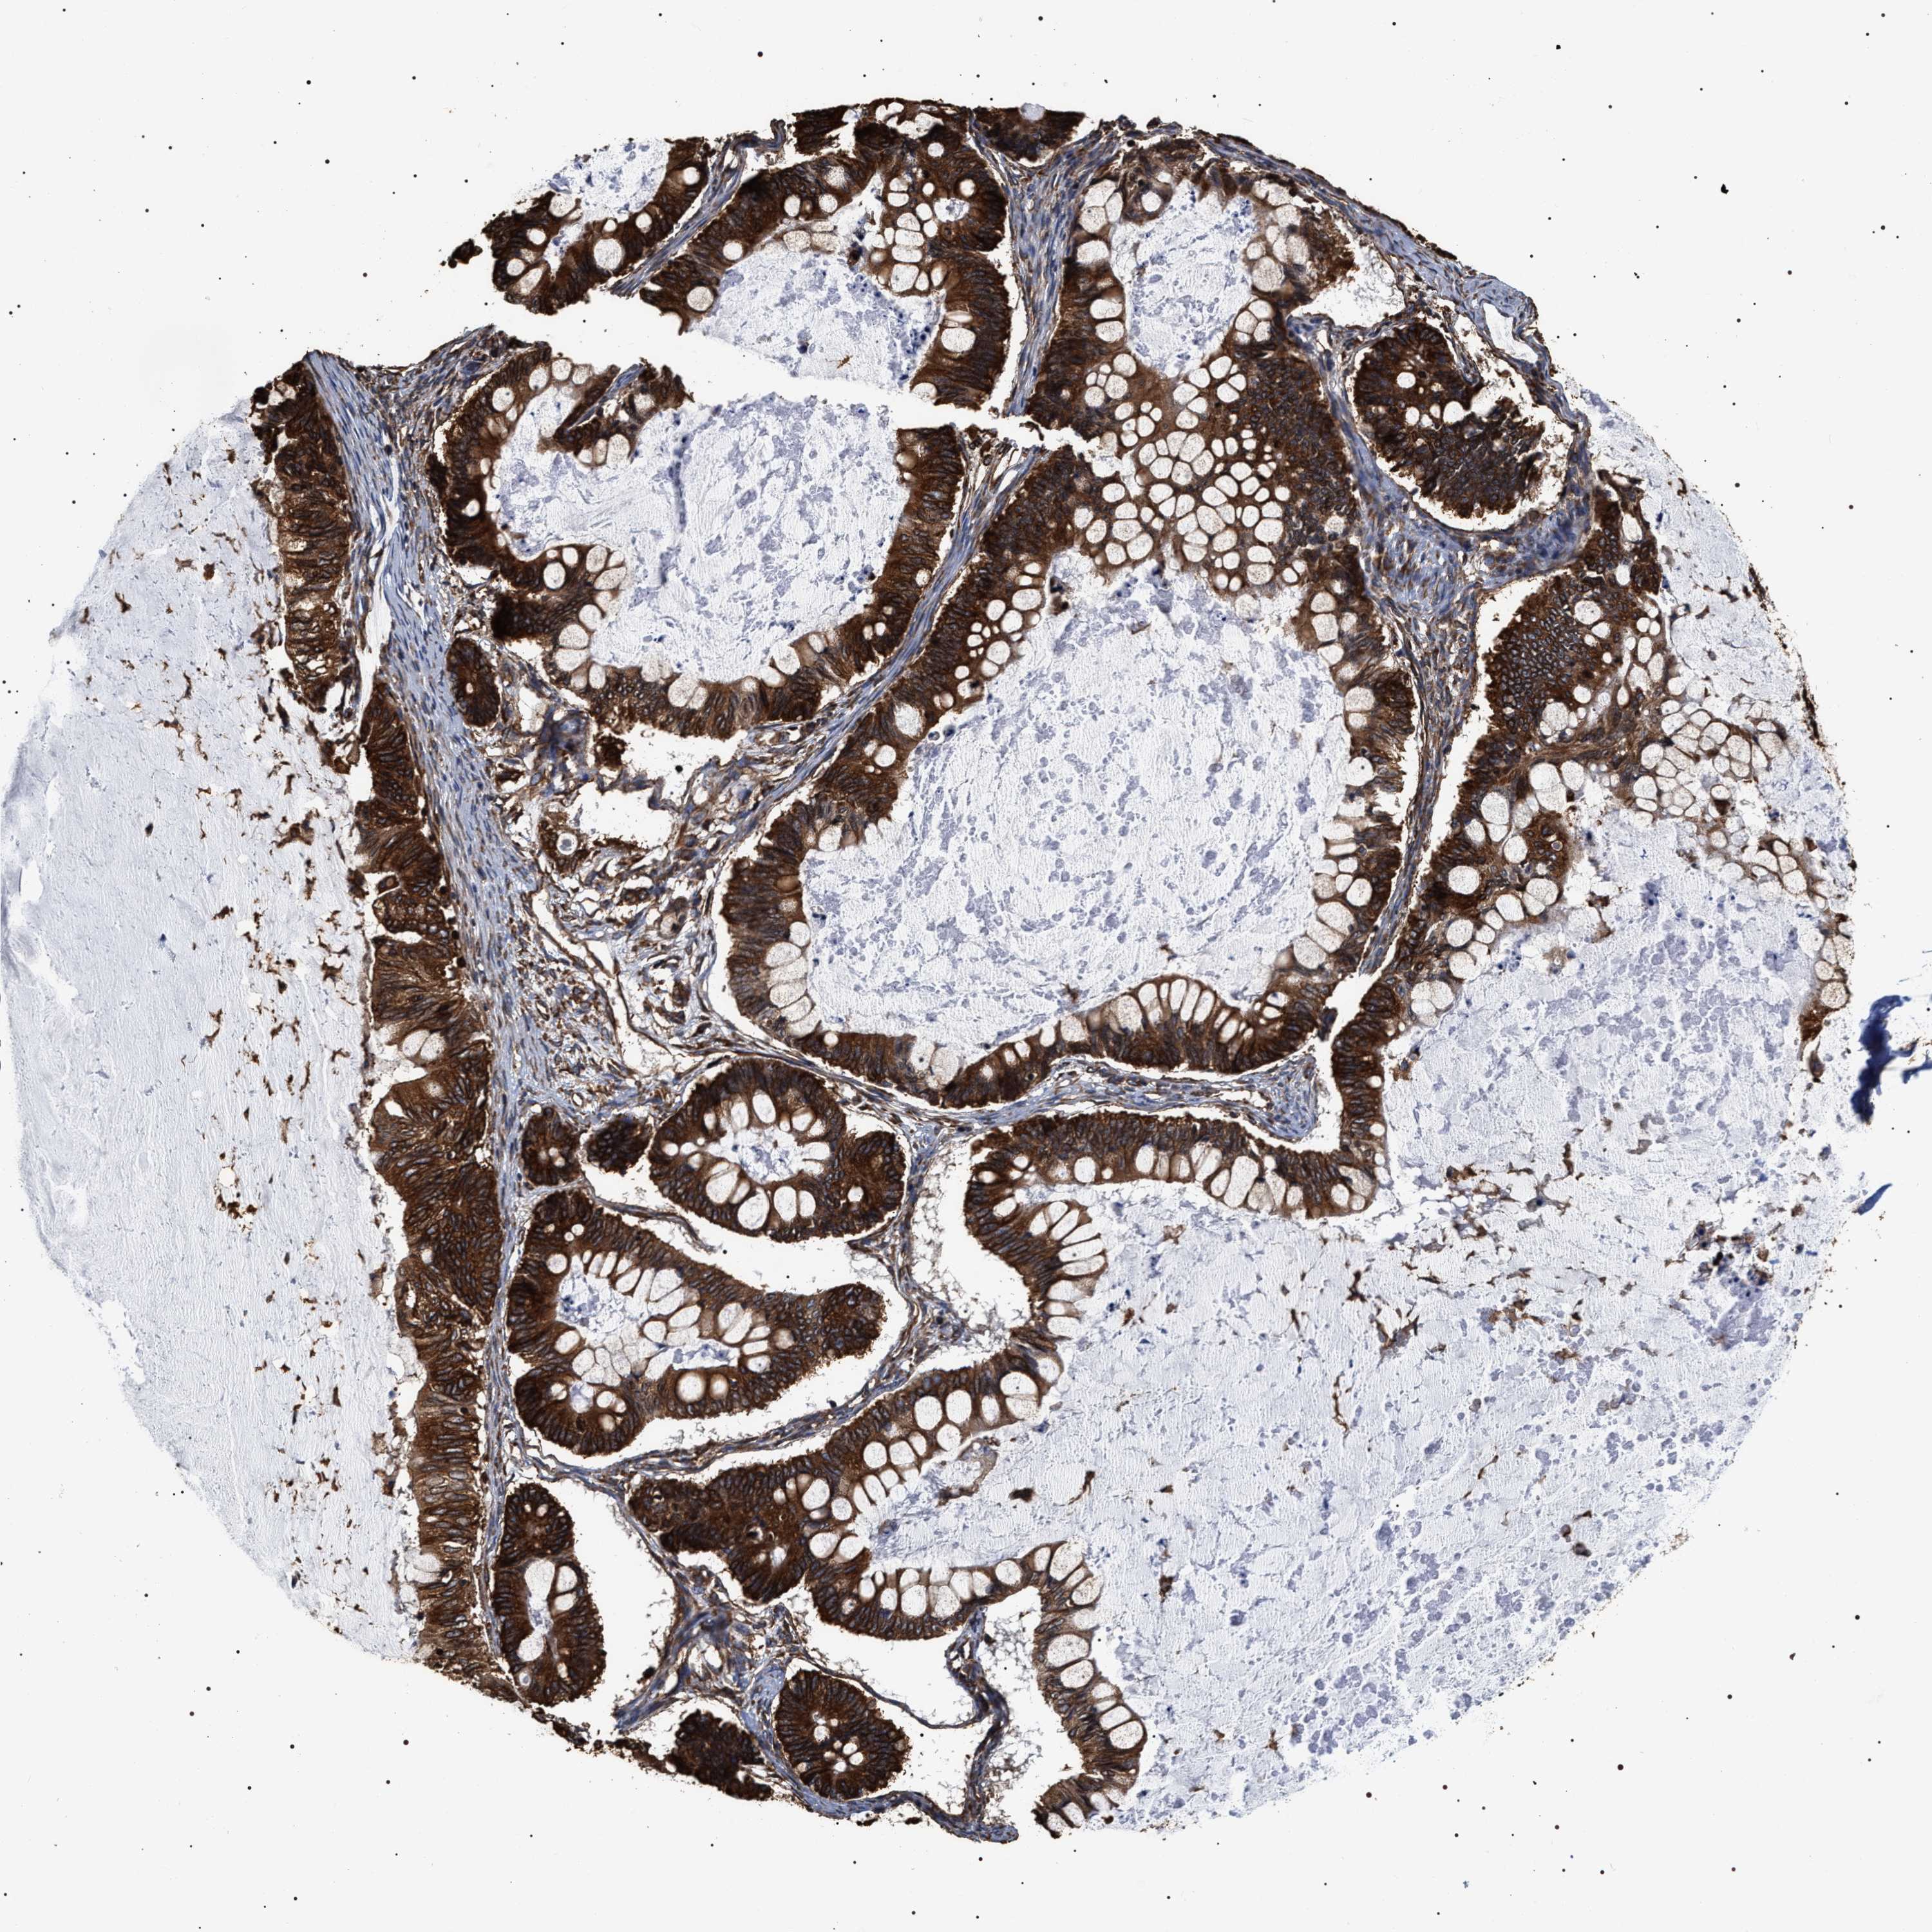

OVARIAN CANCER - Protein expressioni

A mouse-over function shows sample information and annotation data. Click on an image to view it in a full screen mode. Samples can be filtered based on level of antibody staining by selecting one or several of the following categories: high, medium, low and not detected. The assay and annotation is described here.

Note that samples used for immunohistochemistry by the Human Protein Atlas do not correspond to samples in the TCGA dataset.

Antibody stainingi

Antibody staining in the annotated cell types in the current human tissue is reported as not detected, low, medium, or high, based on conventional immunohistochemistry profiling in selected tissues. This score is based on the combination of the staining intensity and fraction of stained cells.

Each image is clickable and will lead to virtual microscopy that enables deeper exploration of all samples and also displays staining intensity scores, fraction scores and subcellular localization as well as patient and tissue information for each sample.

Antibody HPA020559

Antibody CAB026297

Cystadenocarcinoma, serous, NOS

Carcinoma, endometroid

Cystadenocarcinoma, mucinous, NOS

Carcinoma, NOS